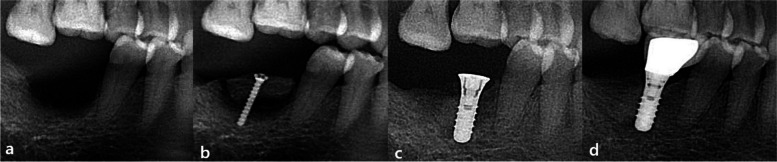

In all three groups, the surgical procedures consisted of two stages: vertical augmentation with autologous block bone surgery and implant placement surgery. The implant placement was performed after a healing period of 4 to 8 months following the bone augmentation (Fig. 1).

Fig. 1.

Block bone graft and implant insertion. a Before grafting, partial edentulous state on the right mandibular molar region (I). b Right after vertical augmentation of RB (T0). c After 4 to 8 months, implants were placed and the crew was removed. d Thirty-six months after grafting (T4), the final prosthetic was completed